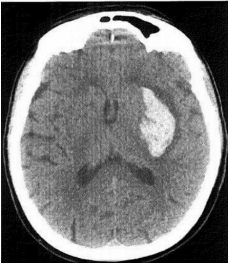

Mulher de 38 anos é levada à emergência após uso de cocaína. Apresenta-se com Glasgow 5, hipertensa e taquicárdica. Após intubação orotraqueal, foi realizado tomografia de crânio que mostrou imagem abaixo. Qual o diagnóstico?